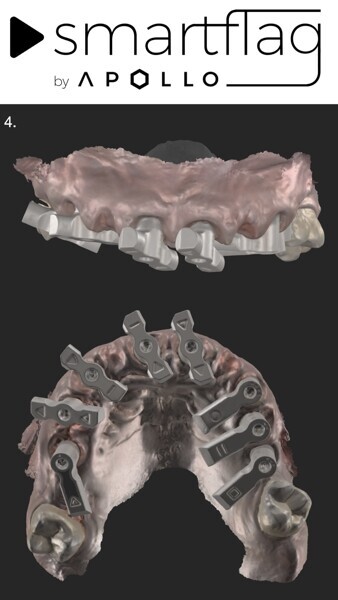

Digital workflows have also brought greater precision and reduced stress for both dentists and dental technicians. The process eliminates many of the complexities associated with analogue impressions, such as splinting impression copings and repeating steps if passive fit checks fail. This was the final analogue step that dentists had to perform, even in the digital workflows we rely on today. Now with SmartFlag scan bodies (Apollo Implant Components), this step has been eliminated, allowing us to transition fully into the digital realm for complex full-arch restorations. By embracing digital methods, we achieve higher accuracy and efficiency, ultimately enhancing the patient experience.

In this specific case, the most significant benefit of digital technology was the ability to execute the surgery, keeping it under the critical 2-hour mark—essential for promoting optimal healing and minimising postoperative complications. This level of efficiency is made possible by the latest SmartFlag scan bodies.

Previously, even with digital workflows, the impression stage remained an analogue process. The use of impression copings and pattern resin was not only difficult but also uncomfortable for patients. More importantly, performing this step intra-orally in fresh extraction sites risked interfering with wound healing, all for the sake of achieving the desired passive fit. Additionally, splinting the copings together was time-consuming and tedious. Today, with digital impressions facilitated by SmartFlag scan bodies, these challenges are eliminated.

3. Placement of SmartFlag scan bodies: We then placed the scan bodies and captured a digital impression with them. The positioning of these scan bodies is critical for accuracy. Designed to reduce the distance between implants, they minimise inaccuracies in digital full-arch impressions. Additionally, each scan body is marked with a specific marking that helps the dentist in scanning and helps the dental technician to identify and correct any mismatches, ensuring perfect alignment (Fig. 27). The SmartFlag scan bodies are not only incredibly efficient but also user-friendly, reducing the scanning time to just 1–2 minutes. Previously, after placing the transfer, we had to splint each implant coping with pattern resin, separate them between implants and re-splint them to avoid tension in the definitive restoration. We also needed to create holes in the impression tray to allow unscrewing of the copings and removal of the impression. In some cases, a second impression with an individualised tray from the dental technician was necessary, resulting in more chair time and additional appointments (Figs. 28 & 29). With SmartFlag scan bodies, all these complications are now eliminated. Furthermore, patients with excessive gag reflexes greatly benefit from this streamlined process because it reduces discomfort.